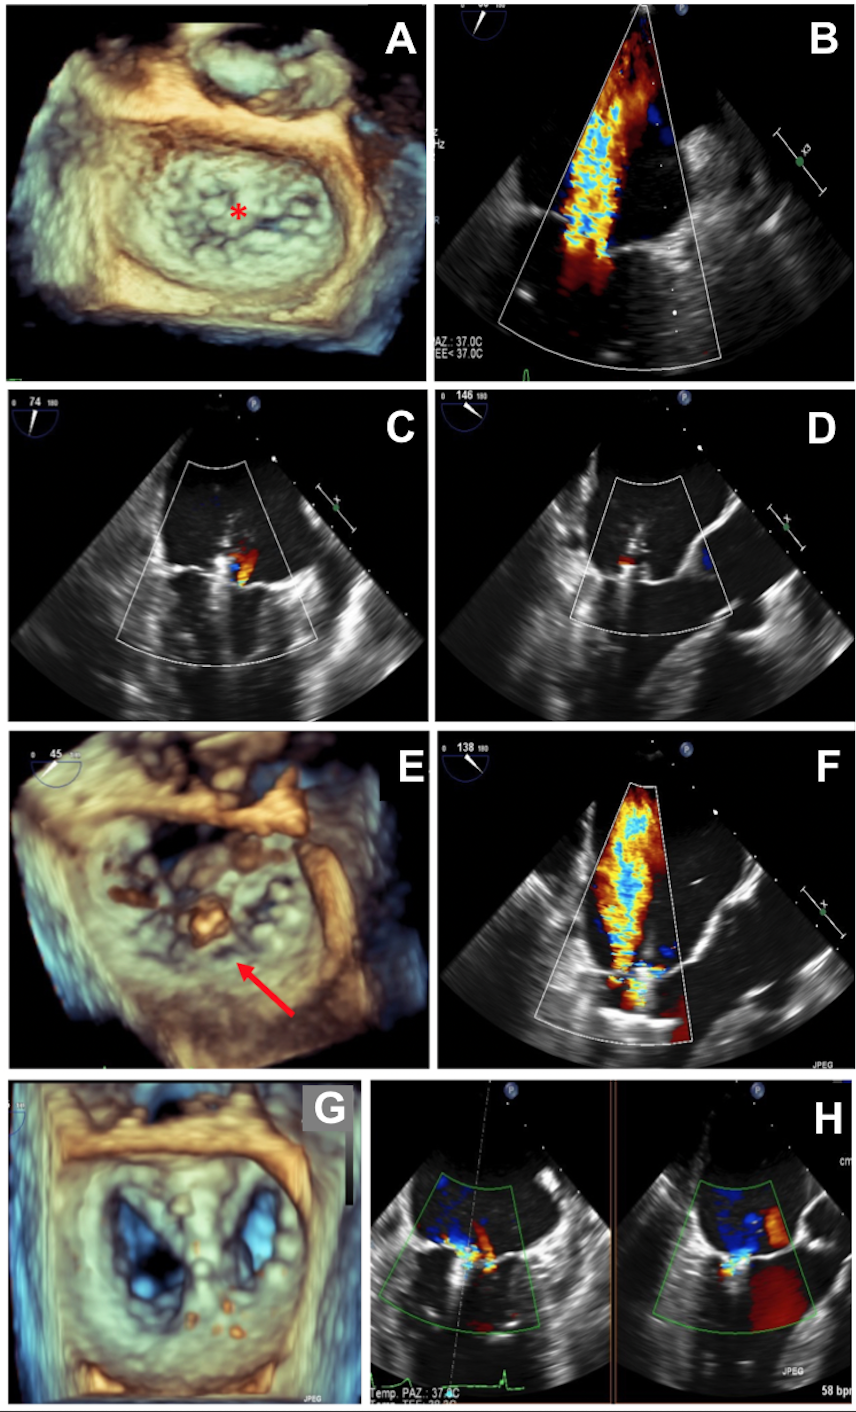

An 80-year-old man was referred to our center for heart failure and severe degenerative mitral regurgitation (MR). Transesophageal echocardiography revealed severe MR due to anterior leaflet prolapse, mainly in its central portion (A2) in the context of fibroelastic deficiency (Panel A,B). Percutaneous edge-to-edge repair was chosen by the Heart Team due to high surgical risk. Using a wide MitraClip G4 XTW (Abbott Vascular), a good grasp with appropriate leaflet insertion and MR reduction to mild was obtained (Panel C,D; Video 1). Shortly afterwards, just before clip release, echocardiography revealed the appearance of a massive regurgitant jet due to a posterior leaflet perforation/laceration just posteriorly to the clip (Panel E,F; Video 2). The patient developed hemodynamic instability with an urgent treatment required. The wide MitraClip was then reopened and a new leaflet grasp included the laceration inside the grasping zone with mild-to-moderate residual MR (Panel G,H; Video 3). Considering the previous laceration, mild-to-moderate residual MR was considered acceptable.

These images underline that a wide posterior leaflet grasp in the context of a fragile leaflet may cause traction forces on the leaflet, which may cause perforation/laceration. Although MitraClip procedure is usually contraindicated in case of leaflet perforation, it can be considered as a bailout treatment option as long as the laceration area is not too far from the leaflet rim and can be included in the grasped area.